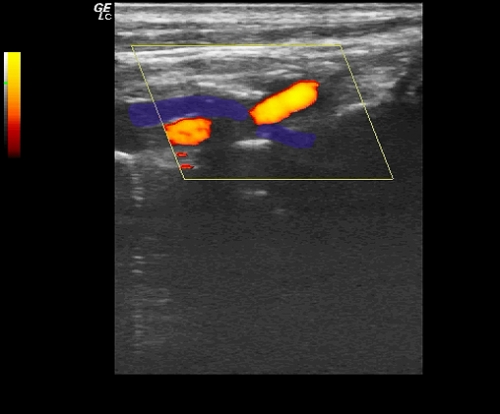

- Что с позвоночной артерией?

Что с позвоночной артерией?

Ваше мнение по этому случаю?

S-образной извитости здесь нет.

Ход артерии нормальный.